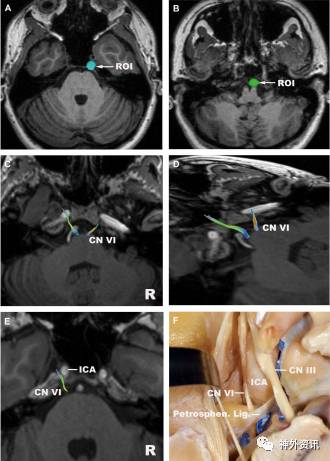

图7. 外展神经。A.ROI置于Dorello管入口处;B.ROI置于脑桥延髓沟毗邻部;C.外展神经(轴向位);D.外展神经(斜位);E.岩斜部外展神经(特写图);F.对应E图解剖示图(上面观)。ICA:颈内动脉;Petrosphen. Lig.:岩蝶韧带。